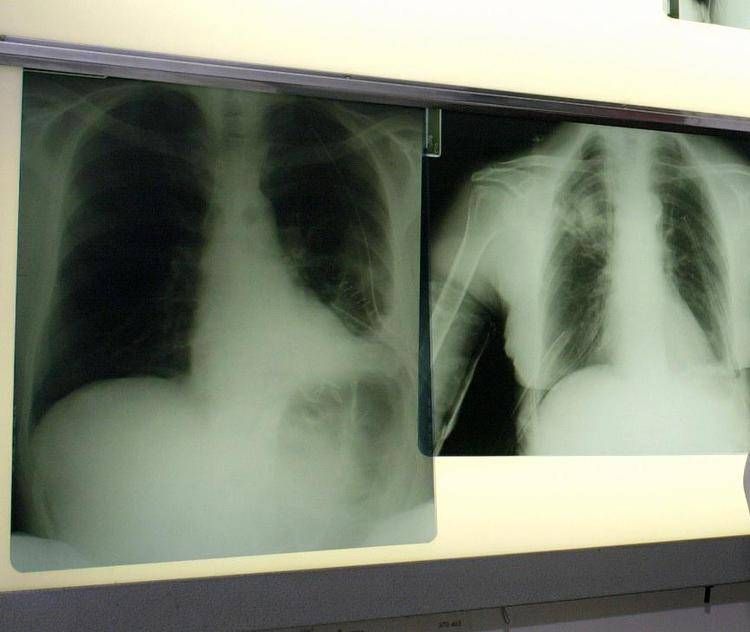

Portare innovazione terapeutica per i pazienti con carcinoma polmonare a piccole cellule (Sclc), una delle forme più complesse di tumore al polmone. E' l'impegno che PharmaMar rinnova in occasione della Giornata mondiale del tumore al polmone, che si celebra oggi, 1 agosto, con il suo approccio "unico e innovativo" ispirato dal mare per la scoperta di nuove terapie oncologiche.

Il tumore al polmone ricorda l'azienda in una nota continua a essere una delle neoplasie più diffuse e letali in Italia e nel mondo. Ogni anno, solo in Italia, vengono diagnosticati 44.831 nuovi casi. Circa il 12% riguarda il carcinoma polmonare a piccole cellule, una forma aggressiva e a rapida progressione, per la quale le opzioni terapeutiche sono rimaste a lungo limitate. Negli ultimi anni, tuttavia, i progressi nel trattamento dello Sclc hanno aperto nuove prospettive. Tra questi, un composto sintetico di origine marina estratto dall'invertebrato Ecteinascidia turbinata che ha dimostrato risultati promettenti in combinazione come terapia di mantenimento in prima linea per i pazienti con Sclc in stadio esteso (Es-Sclc), una delle forme tumorali più aggressive e con maggiori bisogni clinici insoddisfatti. Come dimostrano i risultati dello studio di fase 3 IMforte, presentato lo scorso giugno all'Asco Annual Meeting 2025 di Chicago, il Congresso dell'American Society of Clinical Oncology, il composto sintetico di origine marina, in combinazione con immunoterapia, riduce del 46% il rischio di progressione della malattia o di morte, con una sopravvivenza mediana globale di 13,2 mesi rispetto ai 10,6 mesi con la sola immunoterapia.